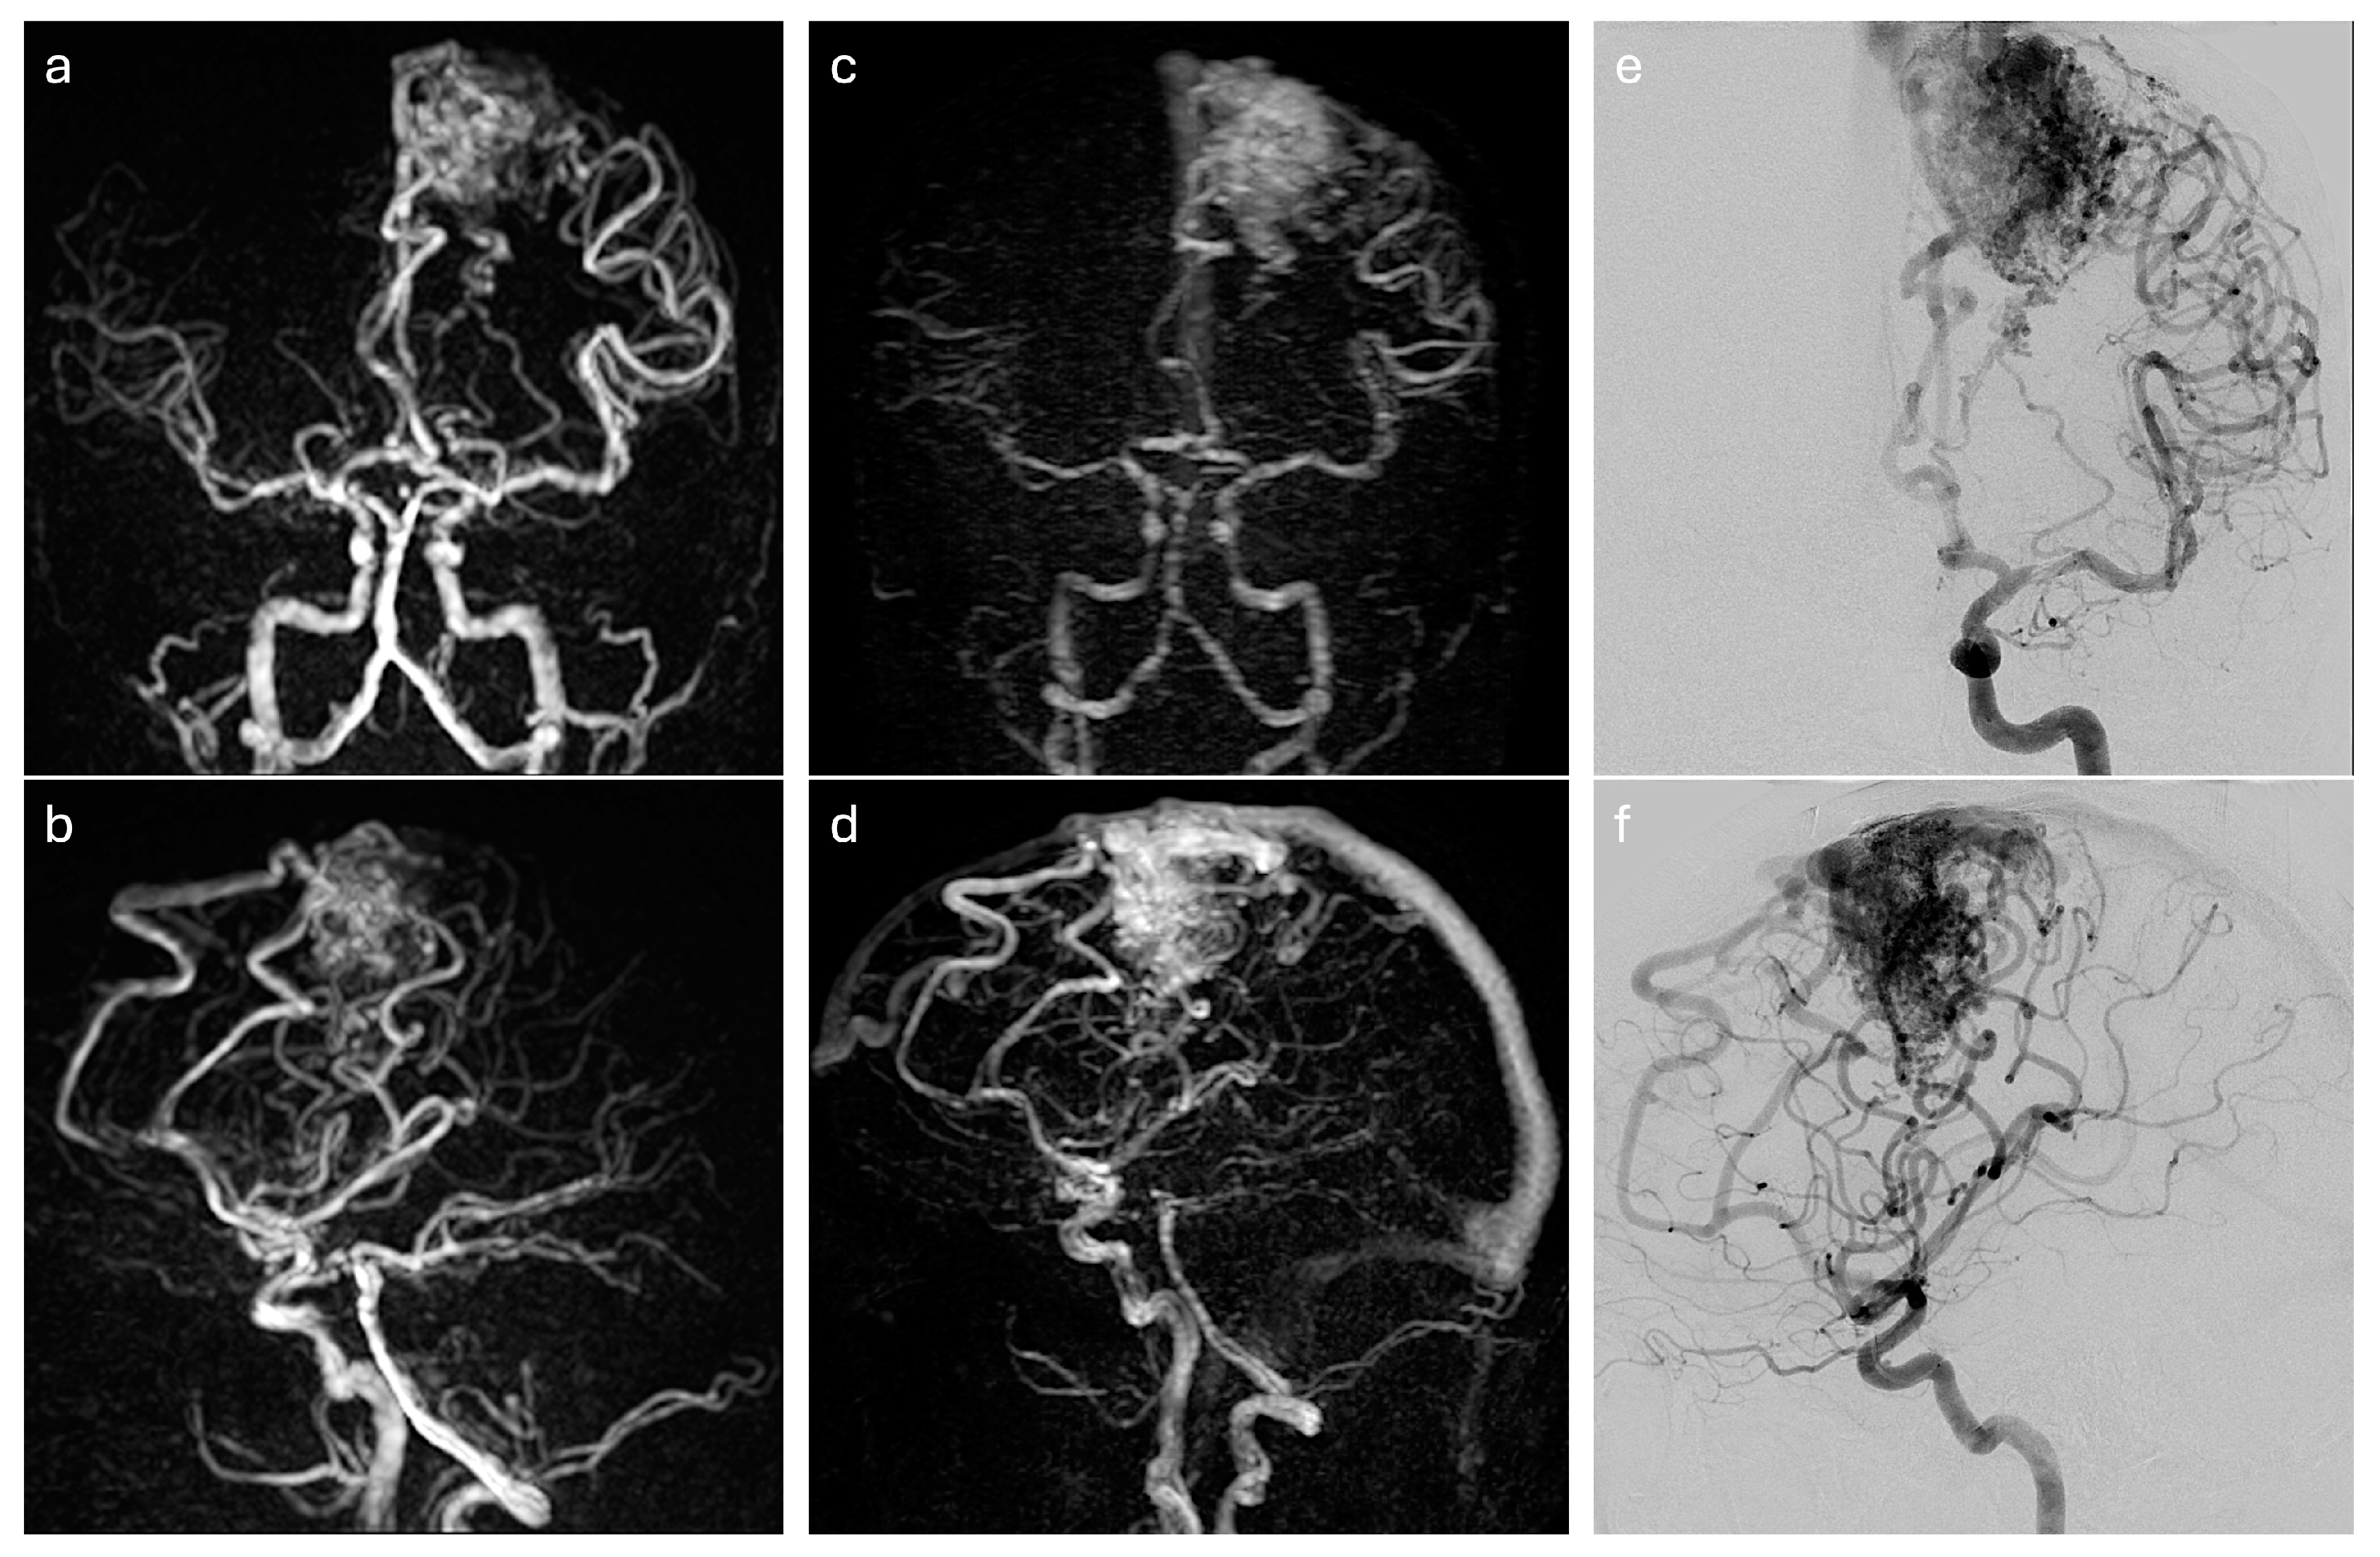

2.2. Four-Dimensional MRA Techniques

2.3. DSA Exploration